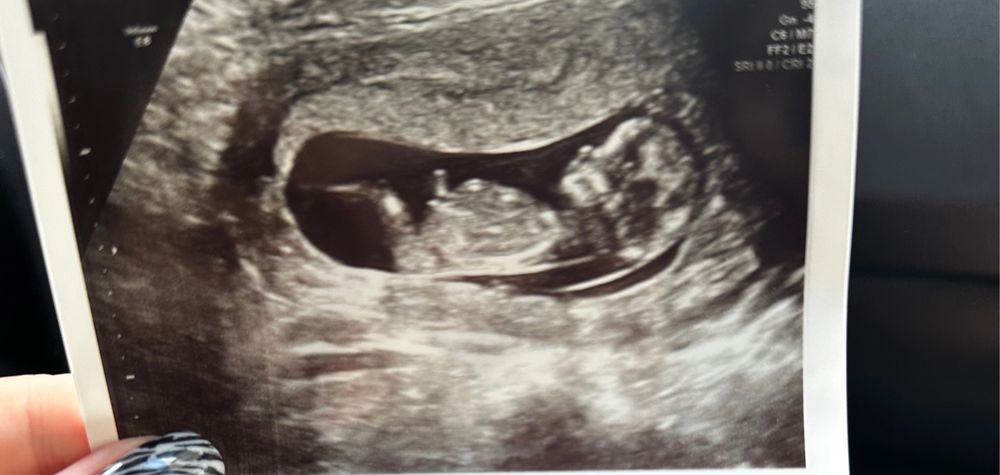

Может кто понимает мальчик или девочка ?

Не видно ничего, сказали правильно, либо мальчик либо девочка )

Не видно половой бугорок, конкретно по этому снимку пол не сказать

На том сроке можно ошибиться или ничего не увидеть. Невтерпеж, сдайте кровь и все узнаете.

Тут не видно)

Низкая плацента Наше первое УЗИ❤️❤️❤️